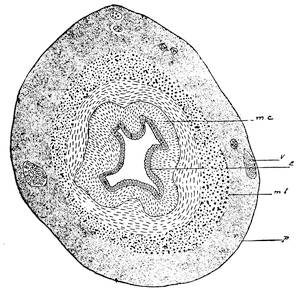

Mons of Venus, labia majora, minora, vestibule, bulbs, clitoris, Bartholinian glands, hymen, vagina, uterus, broad and round ligaments, viiitubes, ovaries, Graafian follicle, ovum.

Function of ovaries, ovum, Graafian follicle, tubes, menstruation, function of uterus, female ejaculation, function of vagina, Bartholinian glands, of clitoris, course of the sexual act.

When the Wolffian body has almost reached its greatest development a second longitudinal duct makes its appearance by the evagination of the ventral surface of the Wolffian body. These ducts lie in close proximity of the Wolffian ducts, along the dorsal aspect of the coelom, or body-cavity, and are known as the ducts of Müller, or the primitive female ducts. The function of these canals in lowly organized animals is that of receiving21 from the body-cavity the ova and of evacuating them from22 the body. The Müllerian ducts also open into the cloaca. At the lower end the Müllerian and Wolffian ducts run in close apposition and form the genital cord. At this stage of development the embryo is thus hermaphroditic like the worms.

The metanephros, or the true kidney, appears first as an epithelial or renal evagination of the Wolffian duct on the dorsal side of the latter and near its opening into the intestinal canal or cloaca. This bud grows forward, extends headward toward the position of the Wolffian body and becomes a long, narrow tube, the ureter. The blind end branches into different tubules, each having a sacculated end. They soon assume a tortuous and convoluted form and represent the permanent kidney. The Wolffian body is now replaced in its function by the true kidney, and enters into special relations with the sexual organs, by being transformed into the genital apparatus of the male.

Before the Wolffian body has yet degenerated the mesothelial cells overlying the free surface of that body, at its upper part, and at the ventro-mesial side, assume a high columnar form and form an elongated swelling, known as the internal genital ridge. As the degeneration of the Wolffian body proceeds the genital ridge is differentiated into the indifferent sexual gland, by producing a projection upon the wall of the coelom or body cavity. This prominence is attached to the surface of the Wolffian body by a fold of the peritoneum. At this stage there is no distinction of sex. The sexual gland represents the indifferent type of the sexual apparatus.

The ovary is produced from the asexual stage by the following metamorphosis. The mesothelial cells on the peritoneal surface of the sexual gland change into the germinal epithelium and form the so-called egg-columns or sexual cord which represent the primitive ova.